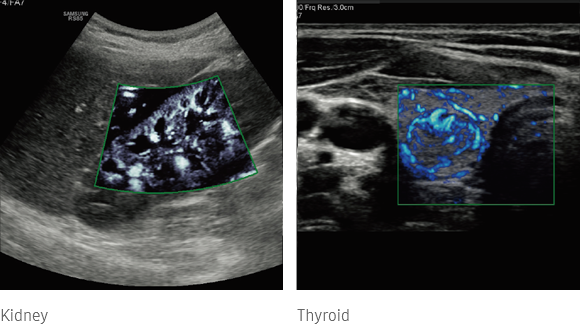

MV-Flow

MV-Flow offers a novel alternative to Color Doppler for visualizing slow flow microvascularized structures.

ultrasound images : S-Shearwave Imaging™ ultrasound images : MV-Flow™

Visualize slow flow microvascularized structures

MV-Flow™ ¹ visualizes microcirculatory and slow blood flow to display the intensity of blood flow in color.

ultrasound doppler  : MV-Flow™

Three dimensional-like visualization of blood flow

LumiFlow™ ¹ is a function that visualizes blood flow in three dimensional-like to help understand the structure of blood flow and small vessels intuitively.